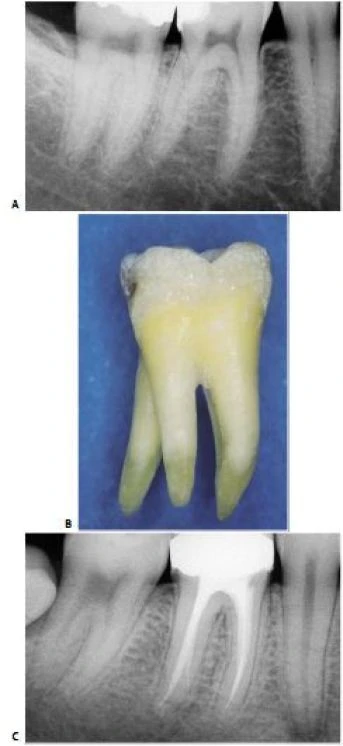

Hình 11.112. Trong một số trường hợp khác, ống tủy gần giữa được thấy ở 1/3 chóp của chân gần.

Hình 11.113. Điều trị lại R46 vì điều trị sót 2 ống tủy: ống xa ngoài và ống gần giữa. A. Phim trước điều trị. B. Xoang tủy sau khi bộc lộ 4 ống tủy. Chú ý sự hiện diện của 1 chỗ lõm ở vùng eo giữa 2 chân gần. C. Một file số 10 đi vào chỗ lõm và  rất dễ dàng đi vào ống tủy gần giữa, ống này có một lỗ chóp riêng. D. Xoang tủy sau khi sửa soạn 5 ống tủy E. Ba file chỉ ra rằng có 3 ống tủy riêng biệt ở chân gần  F. Phim sau điều trị. G. Một góc chụp khác cho thấy hình ảnh 5 ống tủy. H. 7 năm sau điều trị, tổn thương lành hoàn toàn.

Thương tổn trước đây không phải do vật liệu trám ra ngoài mà vì vi khuẩn còn lại trong ống tủy bị bỏ sót.